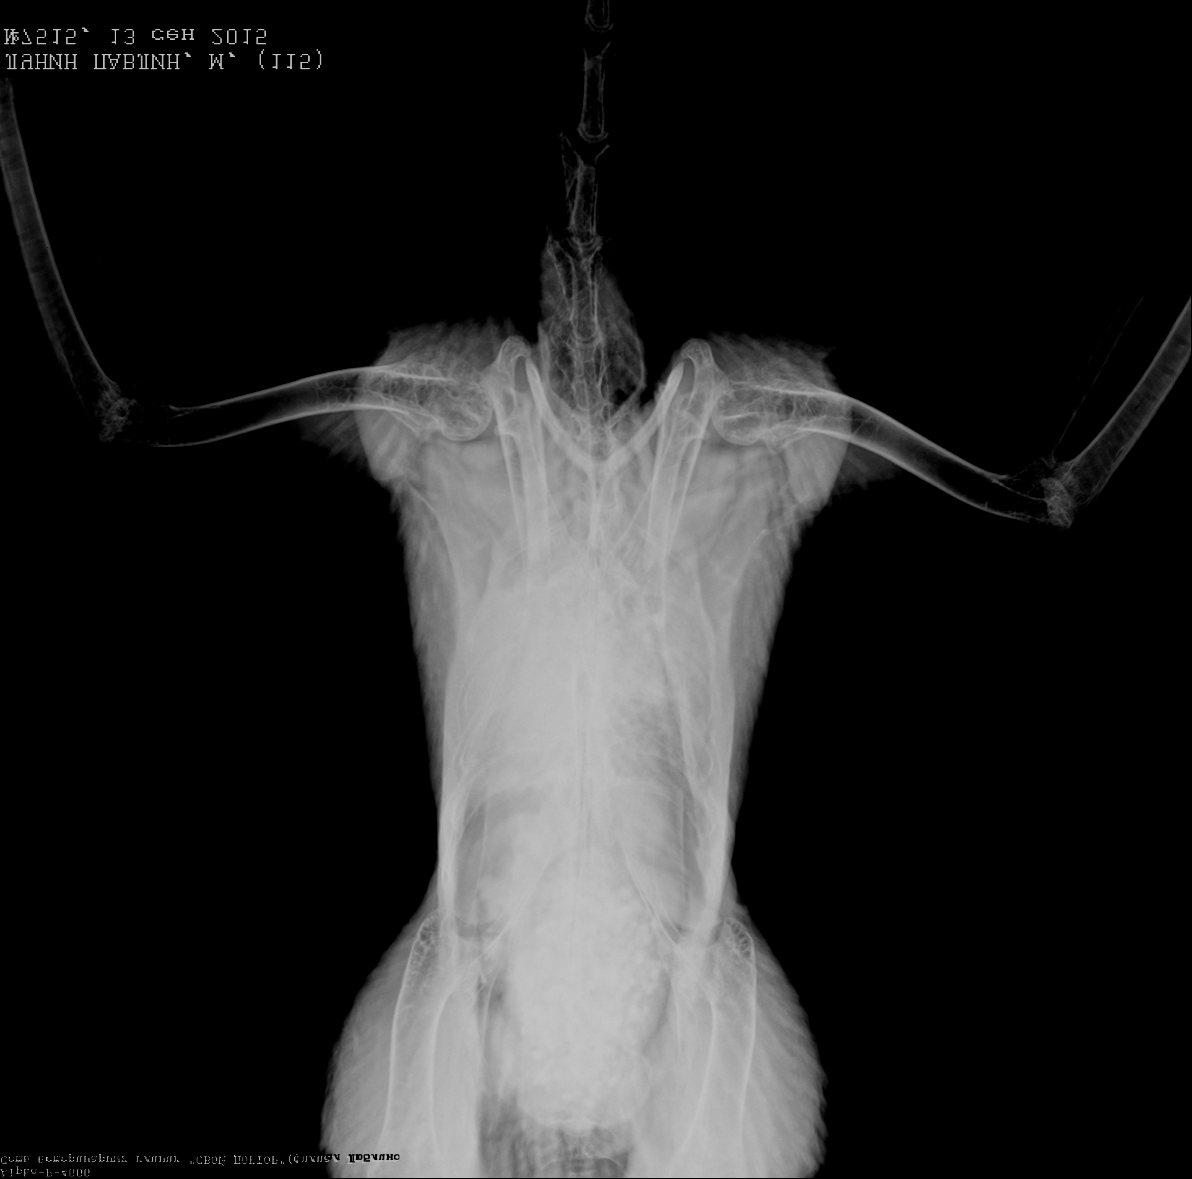

Ко мне на прием попал обыкновенный индийский павлин, с сильнейшим респираторным синдромом(это состояние при котором животным тяжело дышать, Вы видите одышку).

По рентгену у него был полный блок грудных воздухоносных мешков.

Конечно большинство взглянув на рентген сказали аспер!))))

Когда Вы идете на прием ко врачу, не поскупитесь на рентген он дает нам крайне много информации о размере печени, краниальной части почек, состоянии воздухоносных мешков и многом другом, не говоря уже о патологиях опорно-двигательной системы.